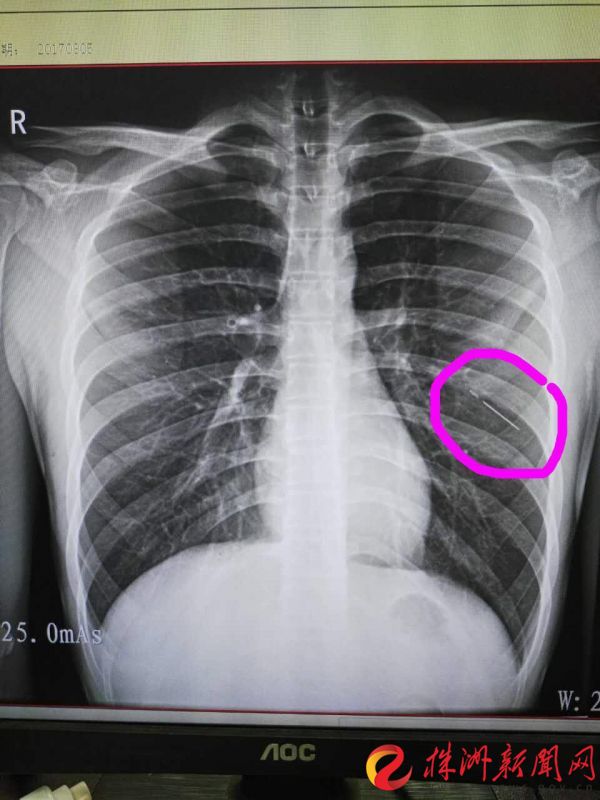

应征青年在体检中发现"胸腔藏针"